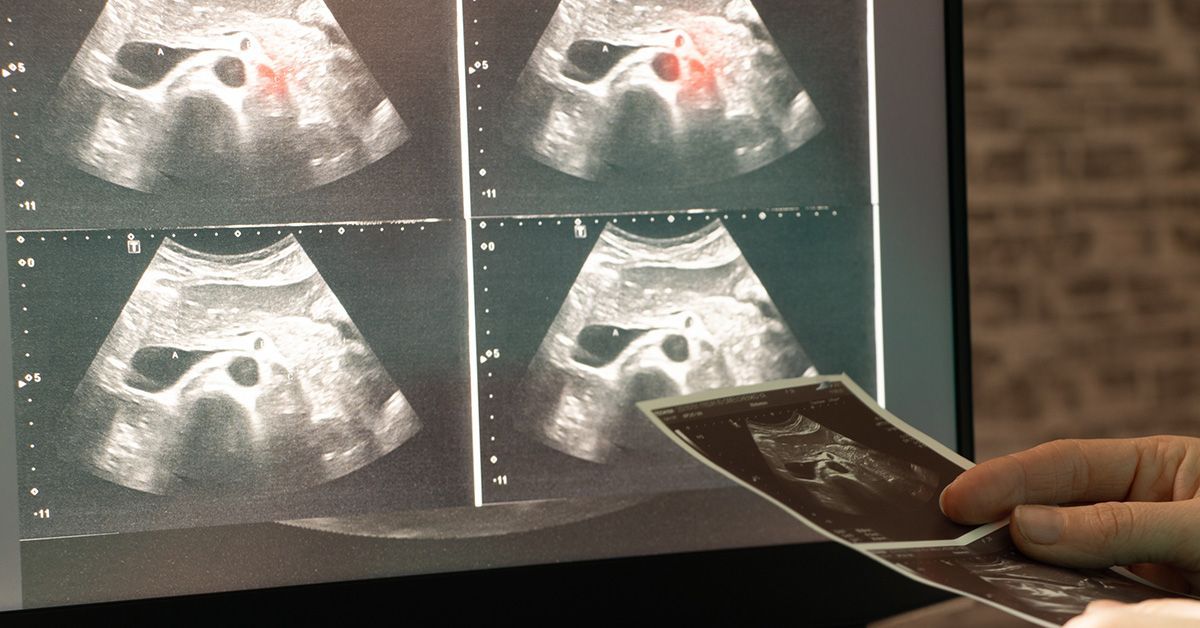

Công cụ AI mới giúp đọc ảnh y tế mà không cần nhiều dữ liệu huấn luyện

Các nhà khoa học tại Mỹ đã tạo ra một công cụ trí tuệ nhân tạo (AI) mới có thể giúp các bác sĩ và nhà nghiên cứu đào tạo phần mềm hình ảnh y tế dễ dàng và rẻ hơn nhiều, ngay cả khi chỉ có một số lượng…